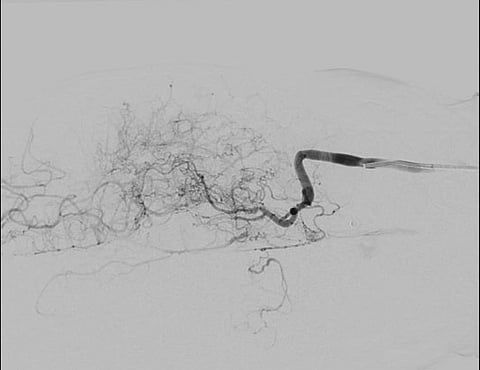

وفي تفاصيل الحالة، أوضحت الدكتورة مريم العتيبي، استشارية جراحة المخ والأعصاب لدى الأطفال والمشرفة على الفريق الجراحي، أن الطفل كان يعاني تضيقًا تدريجيًا في الشرايين الدماغية، مما أدى إلى نقص التروية وظهور جلطات دماغية متكررة.

وبيّنت أن الفريق الطبي أجرى عملية دقيقة تم خلالها توصيل شرايين فروة الرأس بالدماغ على الجهتين، وهي من العمليات المعتمدة في مثل هذه الحالات لتحسين التروية الدموية والوقاية من الجلطات المستقبلية، مؤكدة أن العملية تكللت بالنجاح، حيث اختفت الأعراض واستقرت الحالة العصبية للطفل بعد التدخل الجراحي.